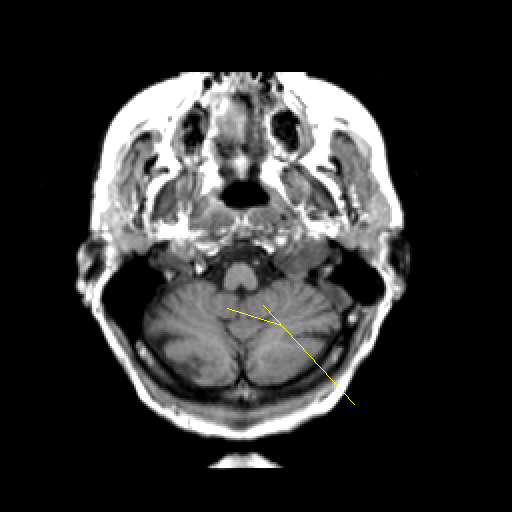

T1-weighted structural MR: Slice 8

Slice 8

Pointers